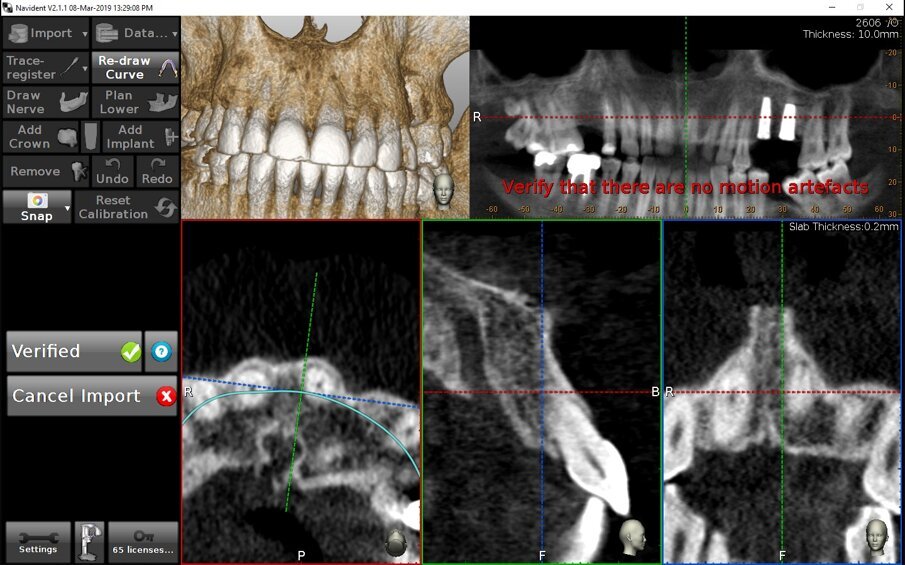

Proprio l’uso di TAC già esistenti al momento dell’accettazione del paziente ci permette di evidenziare alcuni dettagli della chirurgia navigata Navident® by Claronav® che danno il senso del totale controllo che si ha su tutta la chirurgia fin dall’importazione dei dati. Il sistema legge la data di effettuazione dell’esame ed emette un avviso qualora essa sia posteriore ai 30 giorni: specie in presenza di situazioni occlusali instabili i denti potrebbero essere migrati rispetto alla loro posizione nella TAC e ciò è tanto più possibile quanto più tempo è passato dall’esecuzione dell’esame. Una situazione clinica non corrispondente alla TAC non può che esitare in una registrazione fallace e foriera di errori. A termine dell’importazione della TAC, inoltre, richiede di verificare la presenza di eventuali artefatti di movimento; sebbene siamo lontani da un algoritmo di identificazione automatica di questi artefatti, questo passaggio, che può apparire spontaneo a chi pratica da tempo implantologia digitale, è tutt’altro che immediato nel noefita e mette al riparo da errori anche gravi legati alla presenza di detti artefatti (Figg. 8a, 8b).

Figg. 8a, 8b - Esempio di assoluto controllo in chirurgia navigata. Fin dalle fasi di acquisizione dei dati il sistema controlla la loro affidabilità. a) Verifica della data della TAC; b) Suggerimento di verifica degli artefatti di movimento.